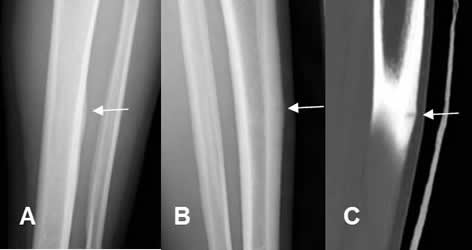

Fig 57 A. Fractura stress.

A: Rx AP, B: Rx oblicua y C: TAC reconstrucción lateral. Imagen en sentido transverso, sobre el tercio medio de la tibia, que corresponde a fractura de stress.